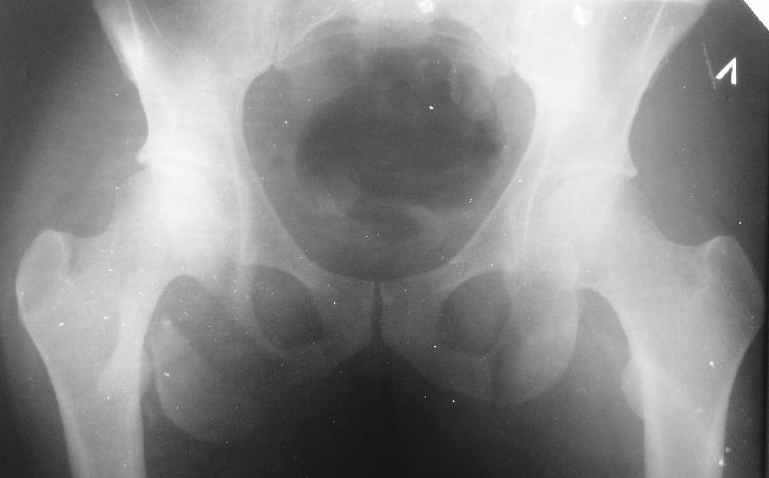

Уважаемые коллеги, хотелось бы услышать ваше мнение по тактике лечения следующего пациента: мужчина, 27 лет, получил травму на производстве 25 июня - перелом правого седалищного бугра (кт и рентгенограмма прилагаются).

Больной жалуется на боли - сидя и при ходьбе. В настоящее время ходит, хромая, без дополнительной опоры. Оторвавшийся седалищный бугор состоит из 2-х фрагментов, один из которых раздражает седалищный нерв. Если кто-то имеет опыт оперативного лечения подобных повреждений, подскажите из какого доступа лучше это сделать. Заранее спасибо.